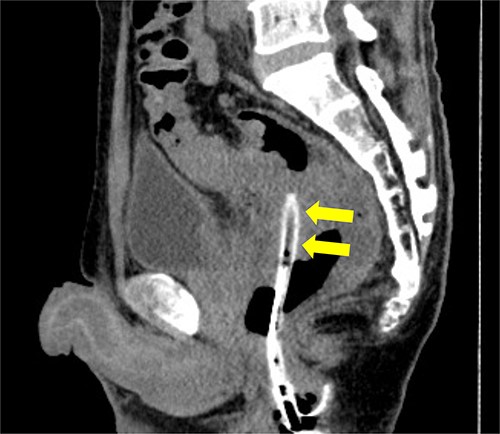

Subsequently, we performed transrectal drainage of the abscess in the lithotomy position without endoscopy. After the incision of the excluded rectal mucosa at 7 cm from the anal verge by the electric scalpel and penetration of the abscess wall by the Kelly clamp, a massive purulent discharge was observed. Next, a transanal rectal drainage tube (MIT drain®, effective length 12 cm; Create Medic Co., Ltd, Yokohama, Japan) was inserted into the abscess cavity without the use of a guide wire, and saline irrigation was performed. After transrectal drainage, the patient’s pain and inflammatory laboratory findings improved rapidly. Pelvic CT showed shrinkage of the cavity 3 days after the drainage (Fig. 3). Bacterial culture test and cytology of the drainage contents revealed negative growth and no malignancy, respectively. The biopsy results showed moderately differentiated tubular adenocarcinoma. The inserted tube was removed on the seventh day after the drainage, and the patient was discharged on the eighth day. In the outpatient department, total colonoscopy revealed that the exclusion from outside the rectal wall on the anal side of the tumor diminished, and the incised mucosa healed as a scar. Ink sticks were marked near the scar on behalf of the combined resection of the tumor. Pelvic CT revealed that the pelvic abscess had disappeared 1 month after drainage (Fig. 4).

Preoperative CT examination one month after drainage. Thickening of the rectal wall is demonstrated (arrowheads); however, the pelvic abscess completely disappeared.